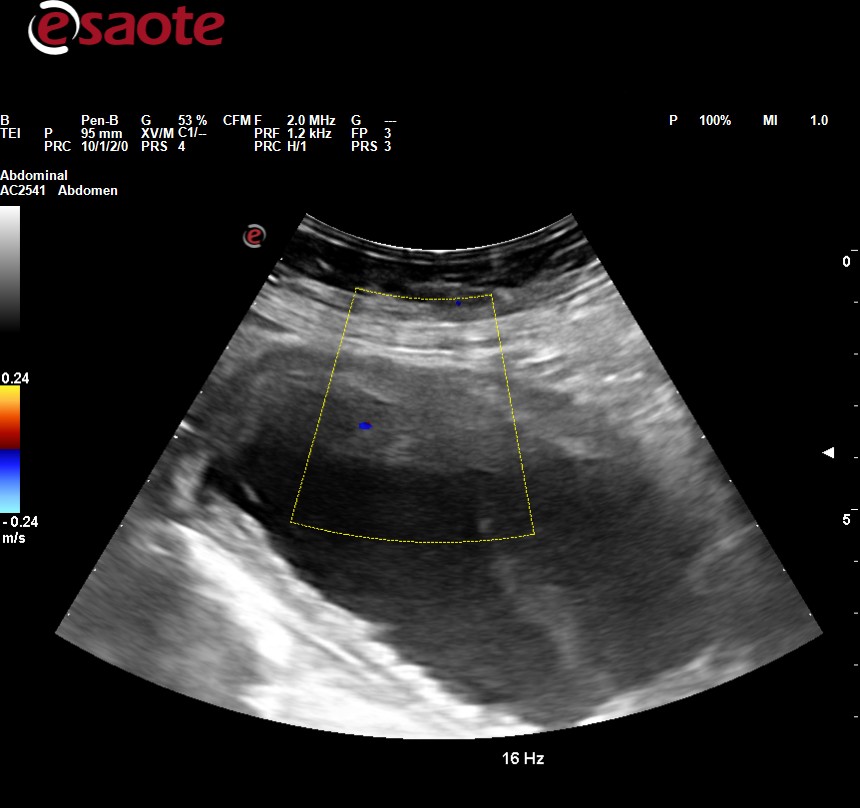

Ecografía clínica abdominal: observamos dilatación ureteropielocalicial bilateral junto con pared engrosada de la vejiga.

JC: hidronefrosis bilateral con engrosamiento de la pared vesical.